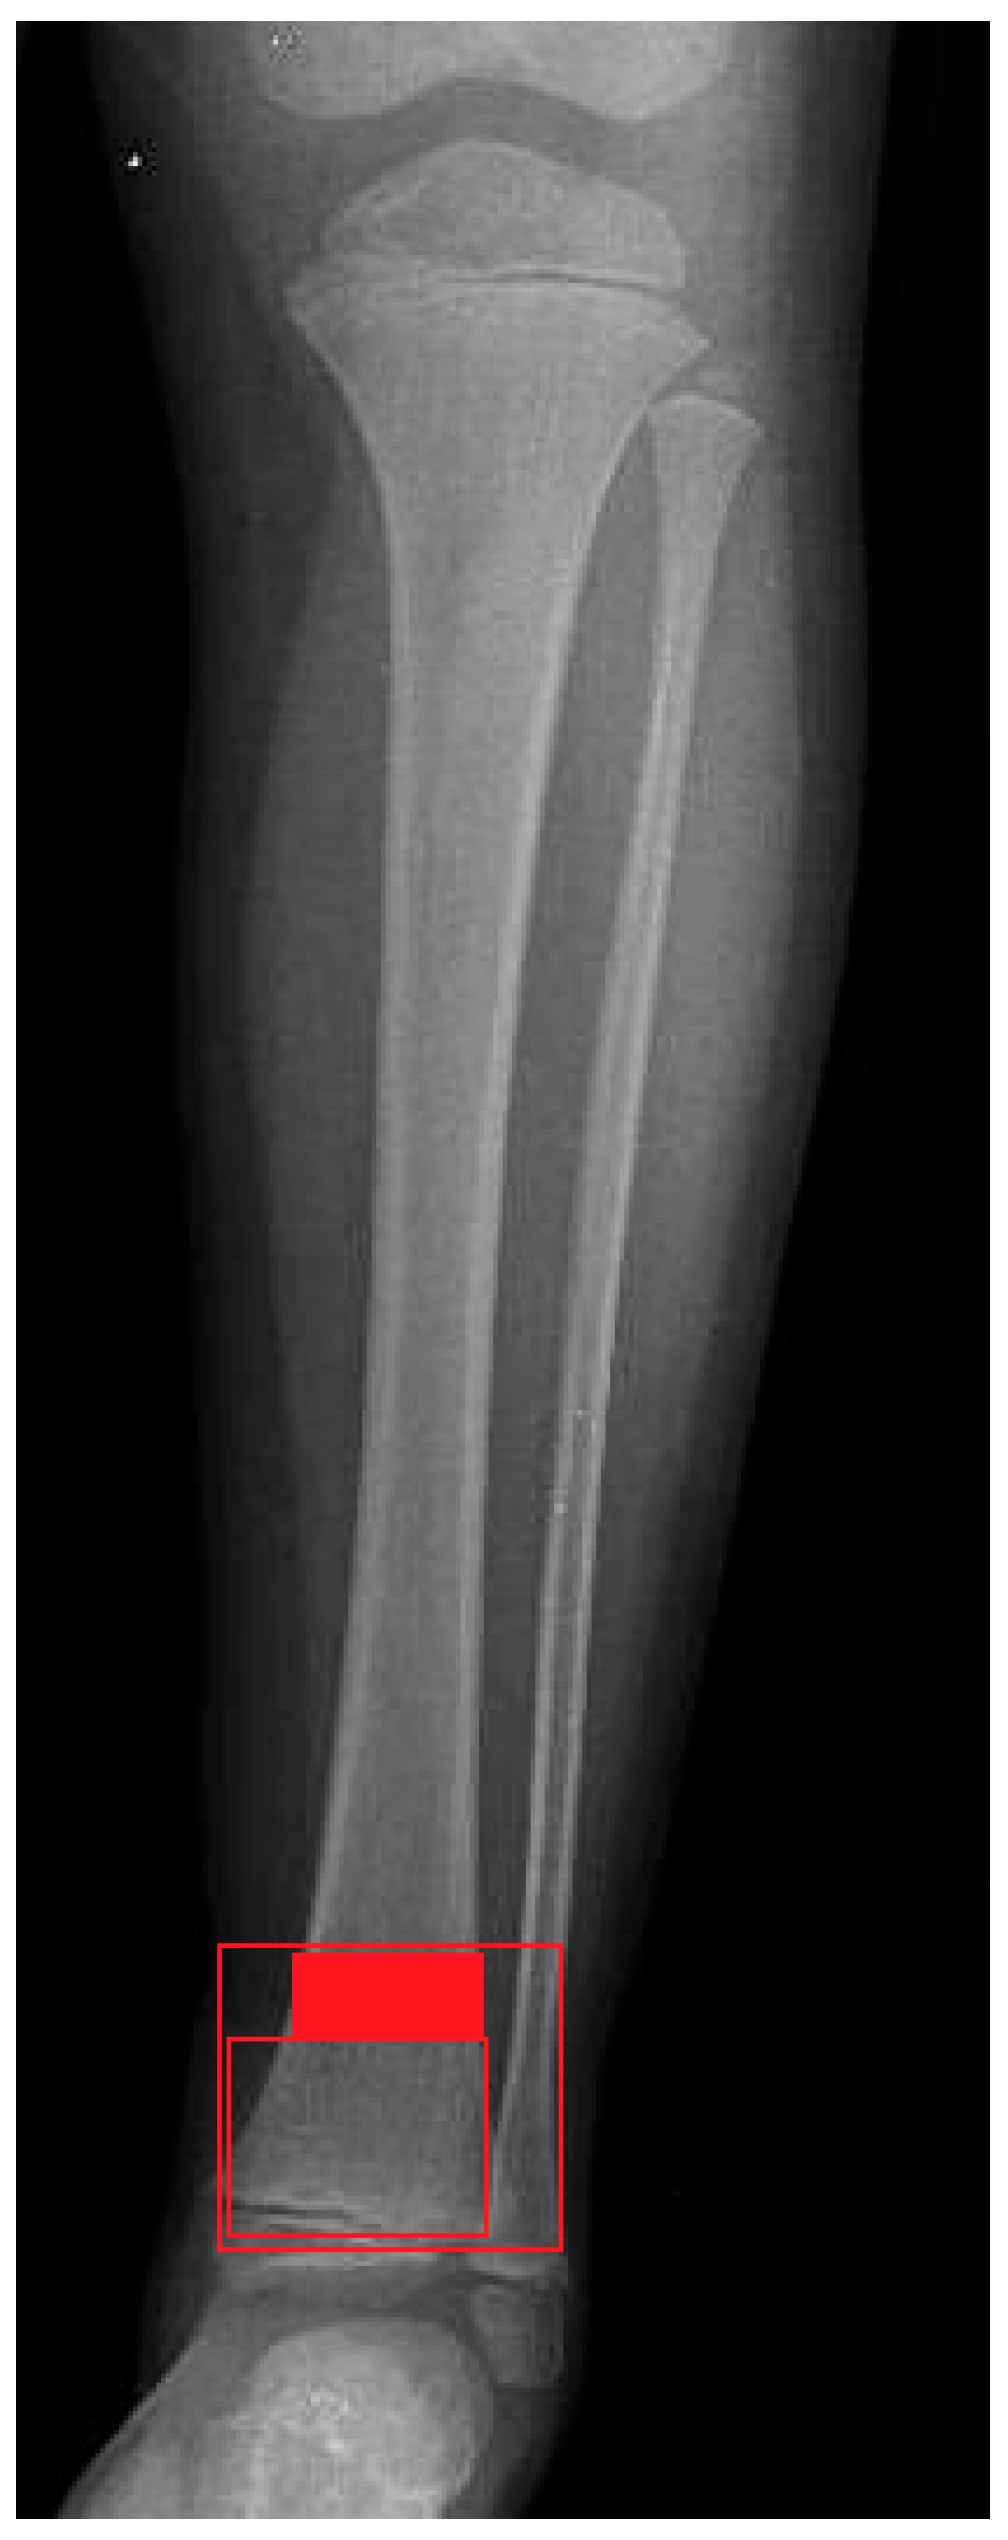

DDMJ is delineated according to “The AO Pediatric Comprehensive Classification of Long Bone Fractures,” wherein the metaphyseal region is represented by a rectangle encompassing the base of the growth plate of both the distal tibia and fibula (the large square at the distal tibia and fibula). Additionally, a smaller square is positioned adjacent to the tibial epiphysis, with a height equivalent to the broadest section of the tibial epiphysis. The region of the distal tibia located between two squares is designated as the DDMJ [,] (Figure 1).

Figure 1.

X-ray depiction of the DDMJ fracture.